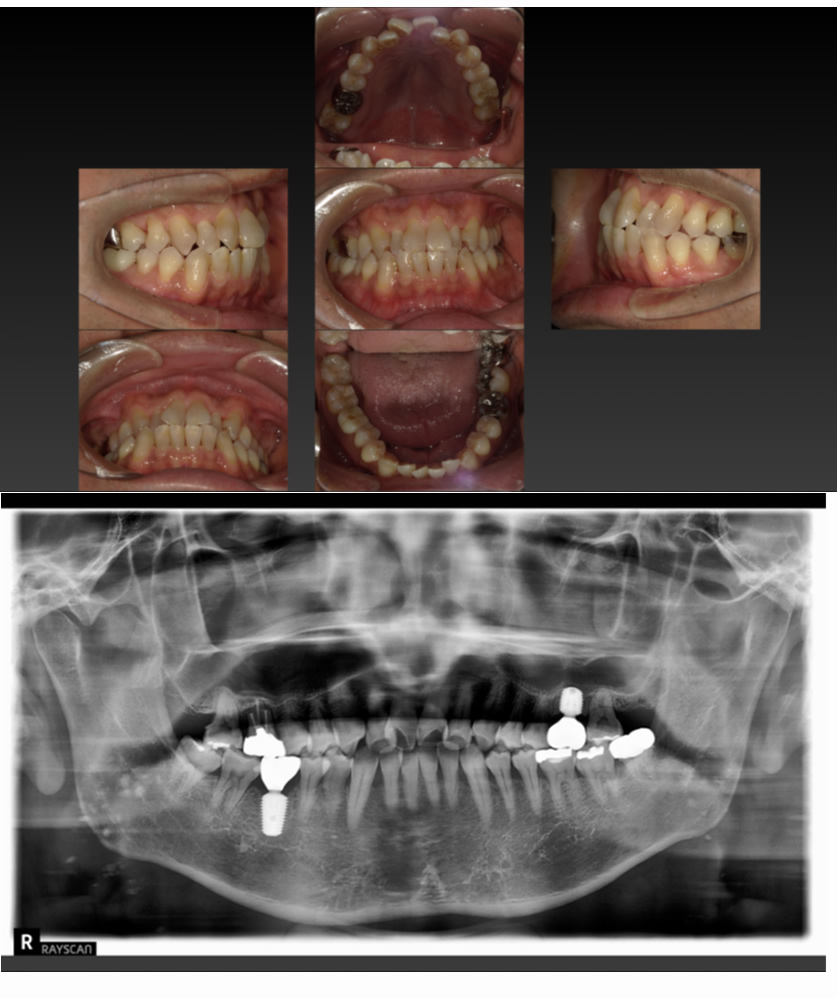

01 症例

仮歯がよく取れてしまうのでインプラントにしたい

Before

After

| 治療内容 | 上の前歯が仮歯で両隣の歯と接着しているが、よく取れるのでインプラントを希望 |

| 患者様 | 60代女性 |

| 主訴 | インプラントにしたい |

| 治療期間(目安) | 3ヶ月 |

| 治療費(税込:目安) | ¥512,000 |

| リスク | 術後に多少の痛みや腫れが出ることがある。歯肉退縮がおきると、歯と歯肉の間に隙間が生じることがあります。 |